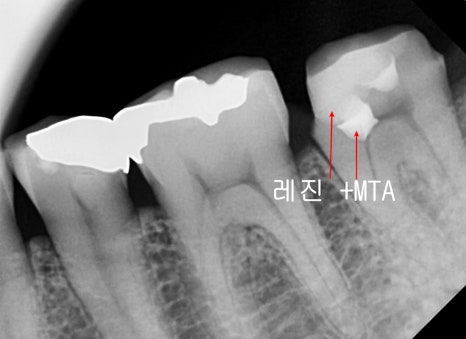

신경을 안정시켜주는 MTA는 강도가 약하기 때문에

그 상부로는 단단한 레진이라는 재료를 덮어줘

치아를 보강하고 그 위에 크라운 치료까지 마무리되었습니다.

과거에 때웠던 치아에 약한 재료가 파절되면서

그 안쪽으로 충치가 진행되면서 신경관 입구가 노출되며 MTA 적용 후 레진 보강 후

크라운치료로 같은 과정으로 치료가 마무리된 케이스입니다.